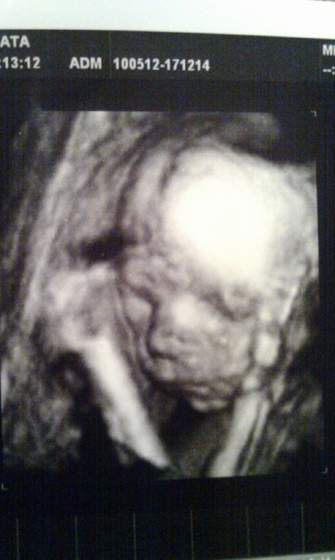

Gratuluję wszystkich udanych wizyt